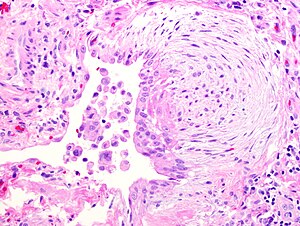

Fibroblast focus in usual interstitial pneumonia. H&E stain. | |

- Fibroblast foci:

- Interstitial inflammation.

- Microscopic honeycombing.

- Typically peripheral - cysts lined by ciliated epithelium.

- Spatial heterogeneity - patchy lesional distribution (areas of abnormal and normal lung may appear beside one another).

- Temporal heterogeneity - lesions of differing age side-by-side.[9]